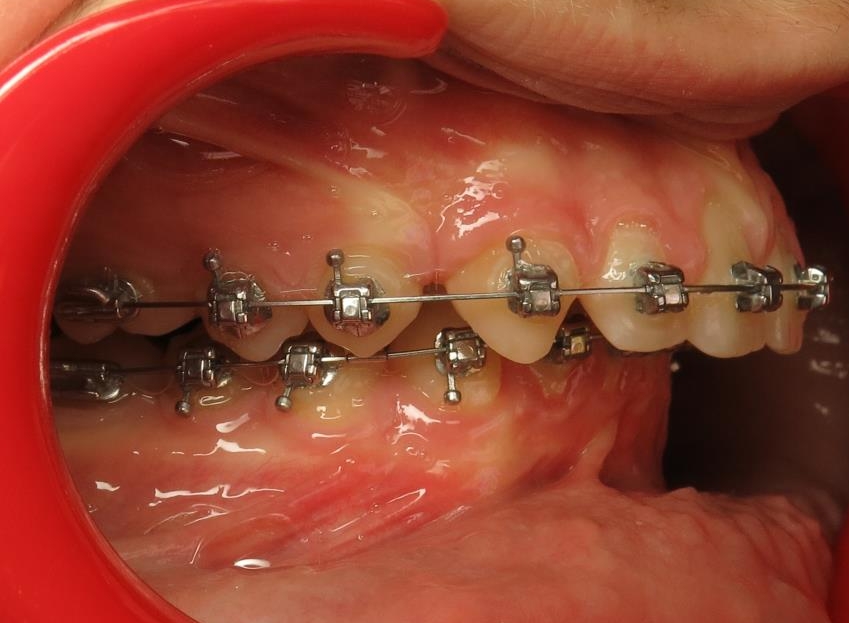

2 - Préparation orthodontique et résultat après chirurgie

Les photos supérieures montrent les arcades juste avant la chirurgie, avec un alignement complet et des axes dentaires physiologiques. La largeur de l’arcade maxillaire a été préparée pour permettre un emboîtement optimal après l’avancée mandibulaire. En bas, les photos post-opératoires montrent des arcades désormais coordonnées, avec une occlusion stable et harmonieuse, grâce à une préparation rigoureuse en amont de l’intervention chirurgicale.